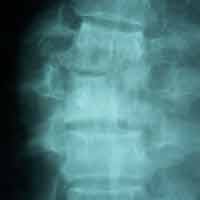

Pre-op Lateral